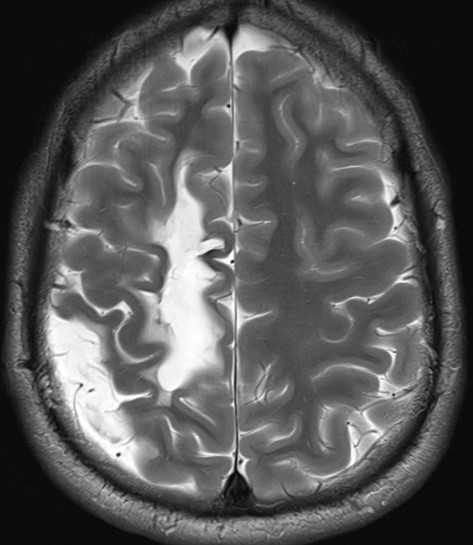

You should then ask the question, Why is the discharge best seen on the left? There are three possible explanations. First, there is a possible transposition of the relevant or even all right and left hemispheric derivations (by carefully analyzing the EEG with the video, especially at times of different artifacts, this possibility can be excluded). Second, perhaps the seizure discharge originated in the left medial central cortex, representing function for the right foot, with oblique propagation to the right central convexity. Third, perhaps there is structural damage to the cortex in the right parasagittal convexity, precluding expression of the seizure discharge from within the superior right frontal-central-parietal convexity. There are several reasons why the third possibility explains the apparent discordance between the EEG and the clinical manifestations. First, notice that the interictal EEG recording demonstrates relative suppression of background rhythms over the left central-periatal region. Second, the patient has a spastic hemiparesis of the left leg and, to a lesser extent, of the left hand and arm. Third, the MRI scan demonstrates evidence of cavitation (loss of cortex) within the superior aspect of the right frontal-central-parietal convexity, related to a haemorrhagic stroke that occurred at the age of seven years:

It should be clear from the MRI scan why the left leg is disproportionately severely involved when compared to the hand and arm, and you may appreciate why the seizure appears over the convexity of the left hemisphere, contralateral to the side of origin of the seizure within the right mesial hemisphere. Hence, the second and third possible explanations are correct.